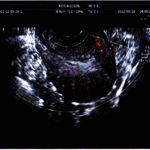

全景四维彩超:子宫增大,肌壁间回声不均。